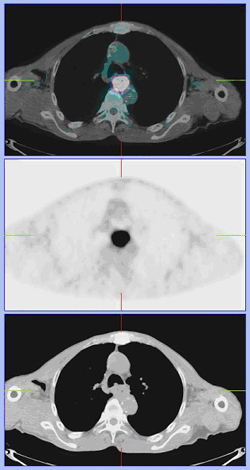

식도암에서 PET 스캔 (PET/CT) 이미지

[식도암에서 PET 스캔 (PET/CT)]

양전자방출단층촬영(PET)은 현재까지 나와 있는 암 검사법 중에 가장 민감하다고 알려져 있습니다. 기존의 검사법에서 밝혀지지 않은 원격 전이의 진단이나 림프절 전이 여부의 판정에 유용합니다.

양전자방출단층촬영(PET/CT)검사는 양전자방출단층촬영(PET)이라는 검사와 전산화단층촬영(CT)을 기계적으로 결합한 검사로서 기존의 양전자방출단층촬영(PET)이나 전산화단층촬영(CT)보다는 진단률이 높으며 암이 전이된 부위의 해부학적 위치를 정확하게 판단할 수 있습니다.